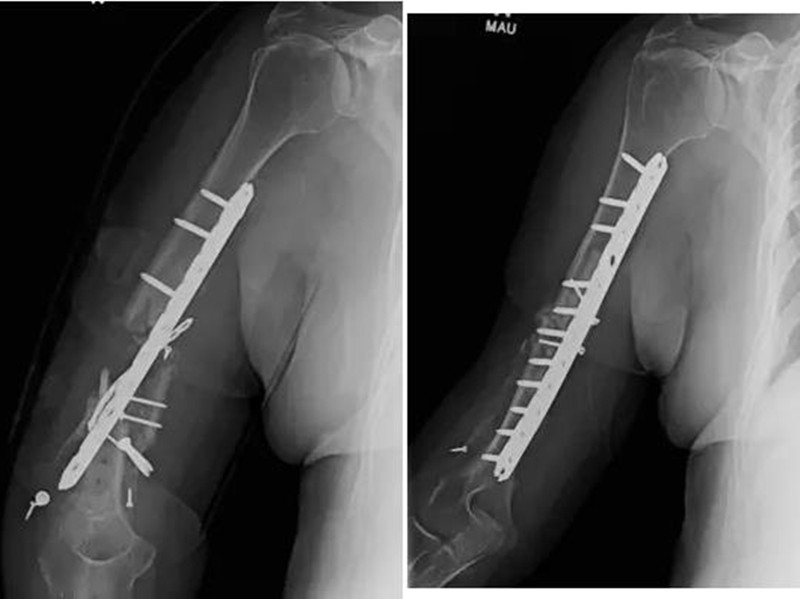

下图第一张图片显示一位患者的骨不连骨折手臂,第二张图片显示已治愈。